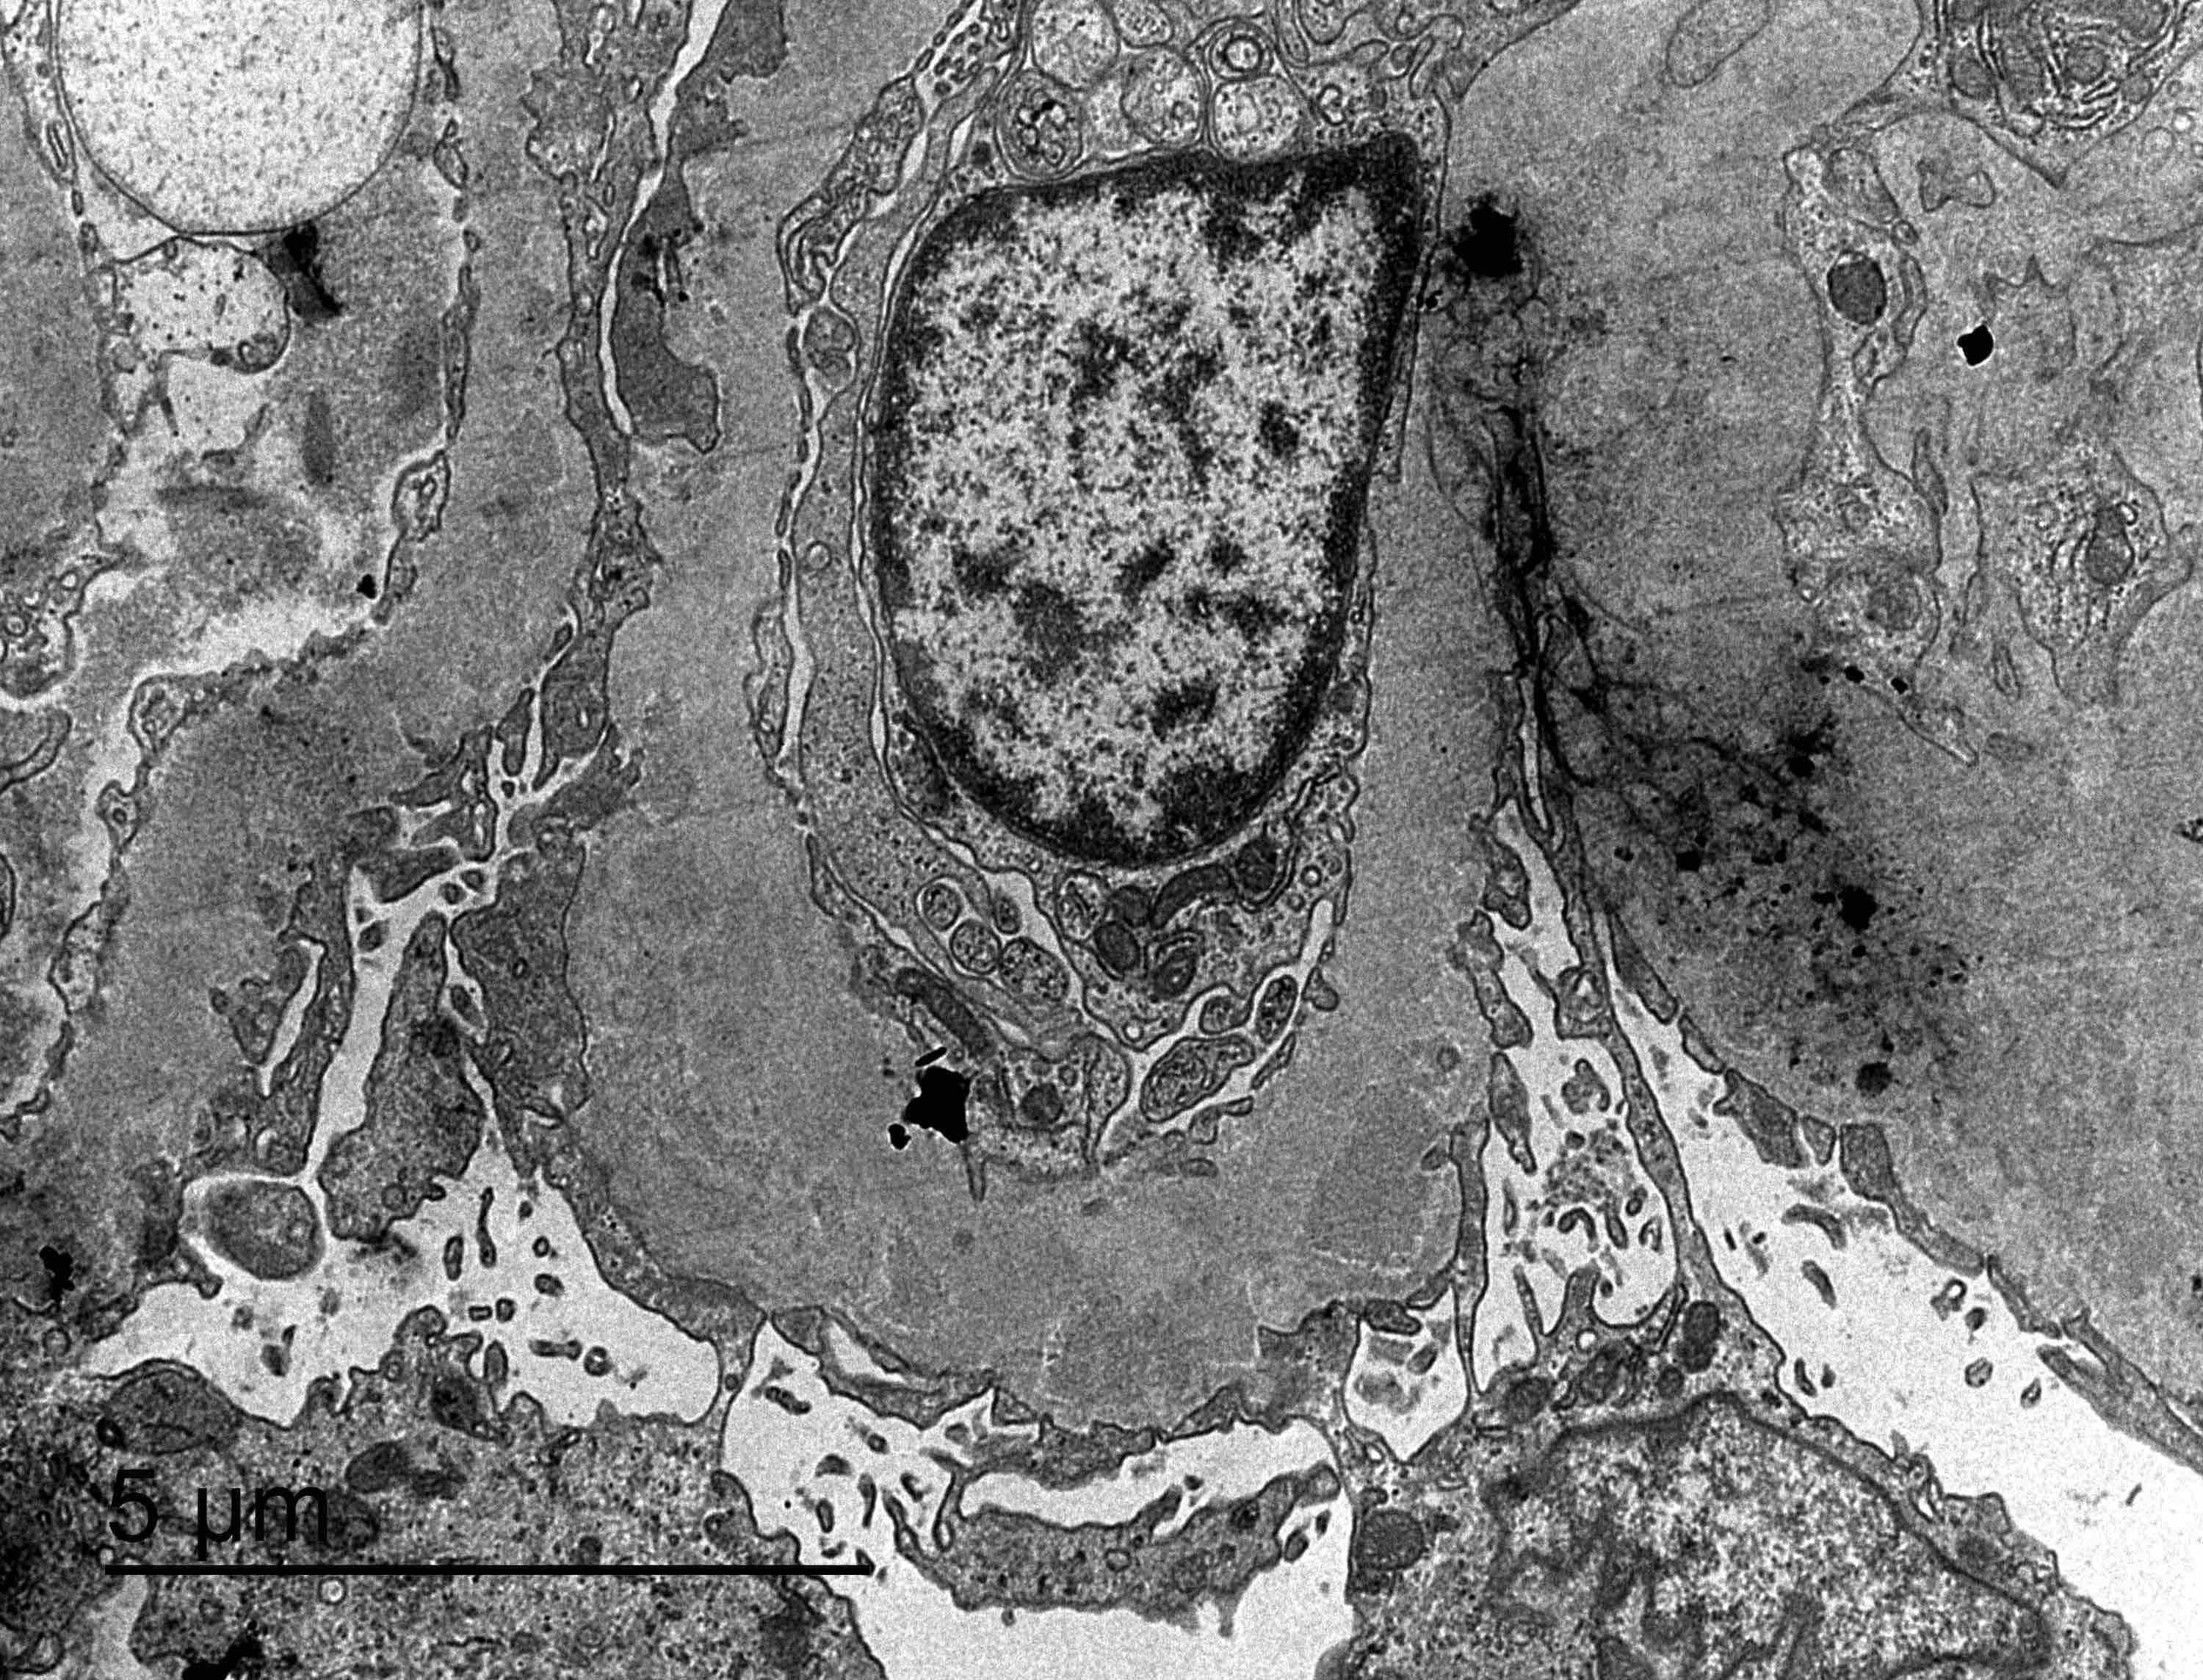

Electron microscopy description

- Electron microscopy confirms the subepithelial localization of electron dense deposits

- 4 stages:

- Scattered electron dense deposits on the epithelial side of the glomerular basement membrane

- Subepithelial deposits with basement membrane material (spikes) between deposits

- Subepithelial (or intramembranous) deposits with basement membrane material between and surrounding deposits

- Electron lucent areas represent probable resorption of prior subepithelial immune complexes

- References: Colvin: Diagnostic Pathology - Kidney Diseases, 2nd Edition, 2015, Zhou: Silva's Diagnostic Renal Pathology, 2nd Edition, 2017

Electron microscopy images

Contributed by Ana Belén Larqué, M.D., Ph.D. and Jonathan E. Zuckerman, M.D., Ph.D.